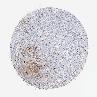

TESTIS CANCER - Protein expressioni

A mouse-over function shows sample information and annotation data. Click on an image to view it in a full screen mode. Samples can be filtered based on level of antibody staining by selecting one or several of the following categories: high, medium, low and not detected. The assay and annotation is described here.

Antibody stainingi

Antibody staining in the annotated cell types in the current human tissue is reported as not detected, low, medium, or high, based on conventional immunohistochemistry profiling in selected tissues. This score is based on the combination of the staining intensity and fraction of stained cells.

Each image is clickable and will lead to virtual microscopy that enables deeper exploration of all samples and also displays staining intensity scores, fraction scores and subcellular localization as well as patient and tissue information for each sample.

Antibody HPA000926

Antibody HPA001578

Staining

High

Medium

Low

Not detected

Intensity

Strong

Moderate

Weak

Negative

Quantity

>75%

75%-25%

<25%

None

Location

Nuclear

Cytoplasmic/membranous

Cytoplasmic/membranous,nuclear

Seminoma, NOS

Carcinoma, Embryonal, NOS